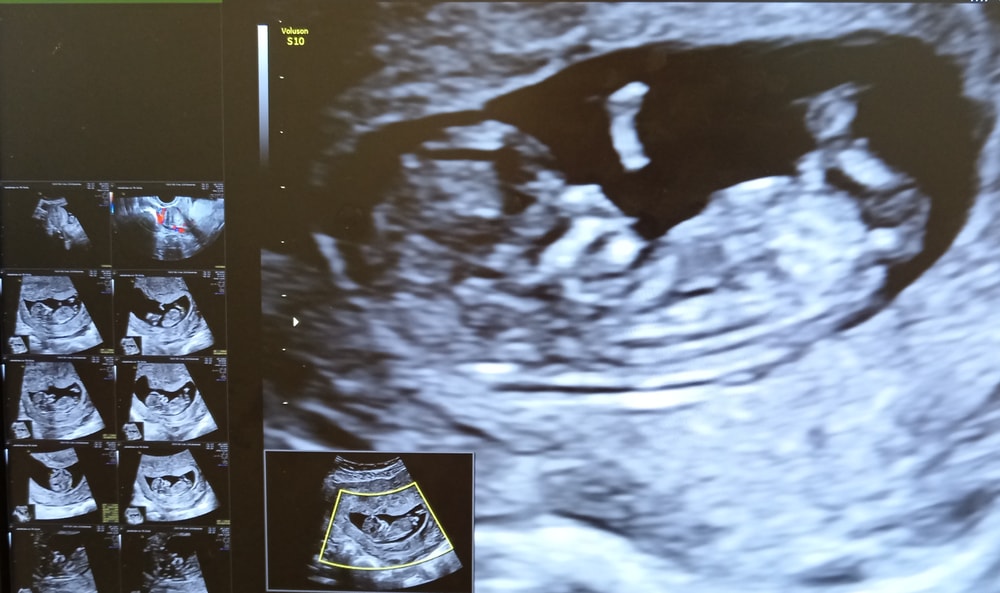

I скрининг

Осмотр в беременность, вопросыБольшой день! УЗИ получилось со второго раза, полезный завтрак мелкий не заценил, отправили докармливать десертом. А вот за сырники, шоколадный сырок, кусок пирога с мясом и кофе мы уже готовы были вертеться и позировать.

По КТР отставание от акушерского срока на 2 дня, поставили 11 нед. 5 дн. Зачатие было на 17-18 день цикла - все точно, как в аптеке 😅

Плацента по заднему краю, пока перекрывает зев.

Не верю я в гадание по половым бугоркам, но узист сказала, что предполагает мальчика. На работе тоже пророчат мальчика, говорят, я хорошею. Никто мне надежд на долгожданную дочь не оставляет 🥲

В остальном все в пределах нормы, носовая кость на месте, воротниковое пространство - ок. Сначала сказали, что в области перешейка - миоматозный узел (до этого не было), но в протоколе не написали. Авось приглючилось.